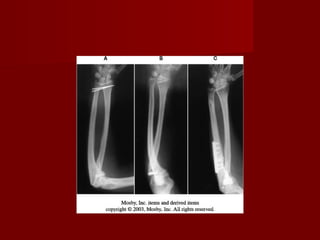

Fracturas de la diafisis del

radio y cubito

   Las fracturas de ambo

huesos del antebrazo

producirá una grave

secuela funcional si no

se trata adecuadamente.

   La pérdida funcional

puede aparecer incluso

tras      la   adecuada

consolidación    de   la

fractura.

Para evitar las limitacion

funcional debe

mantenerse

correctamente las

relaciones:

-   Radio humeral.

-   Radio cubital proximal.

-   Humero cubital.

-   Radiocarpiana.

-   Radio cubital distal.

-   Espacio interoseo

Los metodos de fijación

pueden ser:

- intramedulares.

- Fijación con placas

compresivas o no.

 Si se colocan placas en

radio: en el tercio distal

puede ser anterior y en

el tercio proximal como

esta indicado. En el

cubito es independiente.

Sage

True-flex

ForeSight